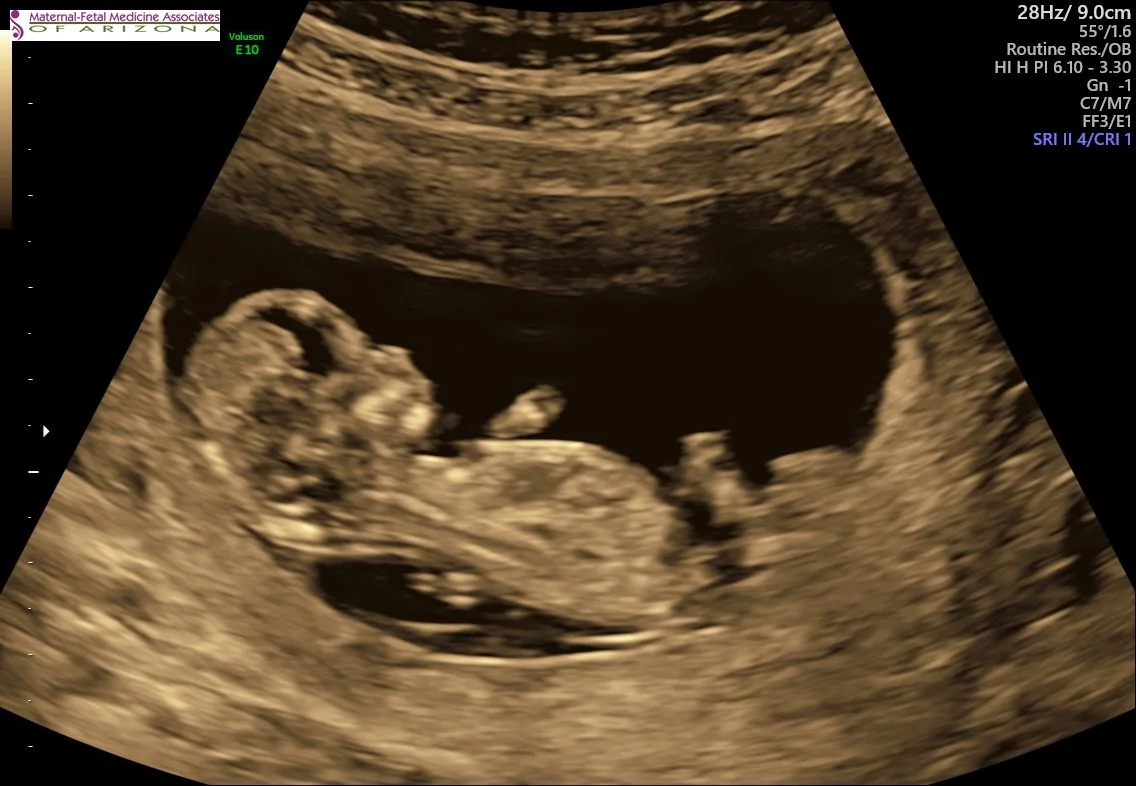

I still remember that weekend like it was yesterday. I was so happy after being so sad for so long. We shared the news with our friends and family and shocked everyone. We have always been very open with people close in our lives about where we were at with fertility treatments. I know some people don’t like to talk about it, but I found it really therapeutic to share. Even though it was not an IVF pregnancy, our clinic was really great about seeing me weekly for check-ups during the first trimester. It was such a relief to see everything progressing weekly and see the strongest little heartbeat. It took some of the anxiety during the first trimester away.